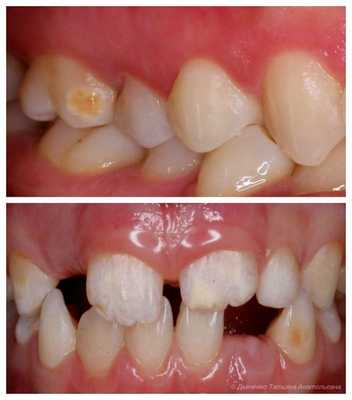

Более тяжелые проявления гипоплазии чаще не заметны при обычном осмотре. Волнистая, точечная и бороздчатая эмаль проявляется после высушивания поверхности. При тщательном осмотре стоматологу становятся заметны чередования небольших валиков и углублений с неизмененной эмалью. Чаще эта форма гипоплазии проявляется в виде точечных углублений в эмали, которые располагаются на разном уровне. В первое время эти участки имеют нормальный цвет, но по мере дальнейшего роста зуба эти участки постепенно пигментируются. В некоторых случаях гипоплазия эмали проявляется в виде одиночной гиперпигментированной полосы на коронке зуба. Иногда эта бороздка довольно глубока и происходит заметное уменьшение размера коронки зуба в виде перехвата, такую форму гипоплазии называют бороздчатой. Очень редко наблюдается лестничная гипоплазия, когда на коронке зубов формируется несколько бороздок. Но характерным является то, что даже при тяжелых формах таких гипоплазий эмали, ее целостность не нарушена.

Реже других изменений встречается аплазия эмали на определенном участке. При этом болевой синдром формируется при контакте с раздражителем и проходит после его устранения. Клинически данная патология проявляется отсутствием эмали на части коронки зуба, но чаще на дне чашеобразного углубления, либо в бороздке, охватывающей коронку зуба. Часто при аплазии эмали имеется и недоразвитие дентина. Это проявляется изменениями формы зубов, характерной для данной группы.

- Эрозивная форма . Эмаль сильно истончена. Дефекты, как правило, округлой, чашеобразной формы, одного размера. Расположены симметрично на одноименных зубах.

- Бороздчатая форма . Отличается бороздчатыми, линейными углубления на поверхности зуба или зубов. Располагаются вдоль режущего края.

- Аплазия — отсутствие эмали на определённом участке зуба. Наиболее серьёзное проявление гипоплазии [10] .